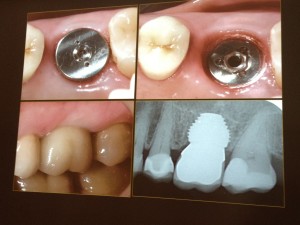

One of the resons I went to Branemark Institiute in South Africa was to hear all about the new MAX Implant. This is the first dedicated implant that has been specifically designed to replace the failling molar. The idea is that the wide body of the implant will fit directly into the socket of the back tooth that has just been extracted. Since the implant is shorter, less bone height is required for stability of the implant. This is especially useful in the upper arch where the sinus is present and in the lower arch where the inferior dental nerve is present. Its success has been proven over the past seven years in South Africa. The first patient to recieve one here is booked for the treatment in April. This could be one of the first MAX Implants placed in Scotland. Another first for No9 Dental Practice. If you have a failing molar why not conact us to see if a MAX could work for you. Peter